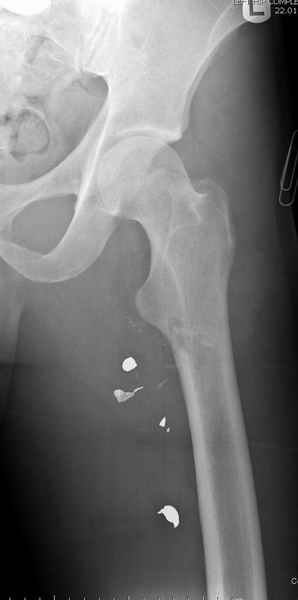

Больной с огнестрельным переломом бедра с вовлечением около 15% медиального кортекса, входное отверстие около 1 см в диаметре; стабильный, без сосудистых и неврологических признаков.

Входные маленькие отверстия от ранении просто игнорируются, никаких дренажей, как любое колотое ранения, они закрываются и были случаи через месяц. Конечно, ведется профилактика открытых ранении: сыворотки и т.д., но еще самое главное уделяем профилактике образования перелома из-за стресса в результате дефекта кортикального слоя.

Учитывая, что больной получил травму не во время визита в церковь, и он является одним из представителем 40 миллионного “outstanding itizen”, без медицинской страховки, без работы в свои 39 лет, и без надлежающей ортопедической дисциплины у которого отсутсвует страх стрессового перелома, было рекомендовано оперативное лечение: профилактическое антеградное интрамедуллярное штифтование.

Методика штифтования при отсутствии большой зоны перелома как при онкологических профилактических штифтованиях, расверливание интрамедуллярного канала проводим с предварительным наложением дополнительного дренажного отверстия в дистальном отделе бедра (в данном случаи в канале оставили 6.5 мм канюлированный шуруп), иначе при создании давления в канале во время сверления имеется опасность эмболизации легочной артерии тромбом.